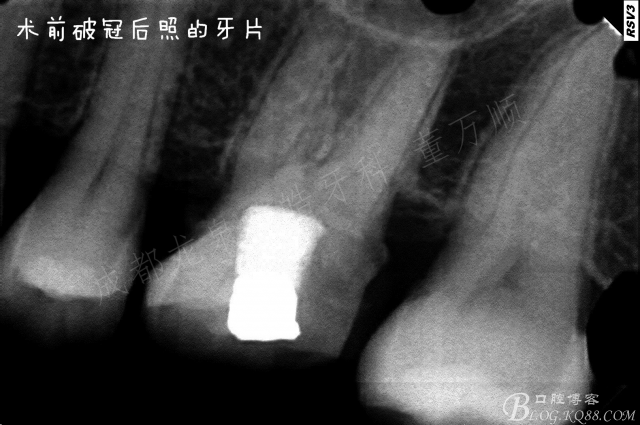

龋坏面积非常大 患者是在日本留学的时候做的治疗,由于当时没有及时的复诊导致现在的情况 ,患牙有明显的自发痛症状,阵发性钝痛。

对侧已经完善根管治疗,做的金属嵌体,边缘非常密合 很 抱歉没有保留其金属嵌体口内照。